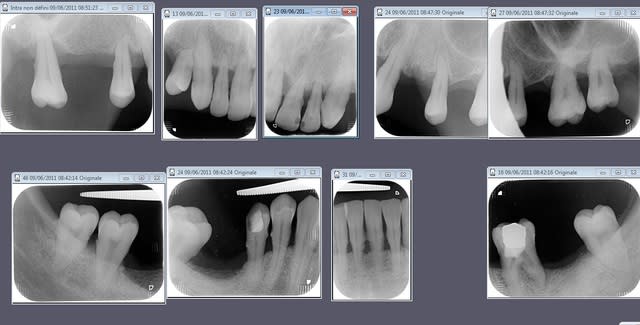

je vous joins juste un bilan retro car la pano est argentique et merdique .

vous faites quoi dans ce cas en imaginant la pano (je sais vous aimez pas mais bon allez un effort)